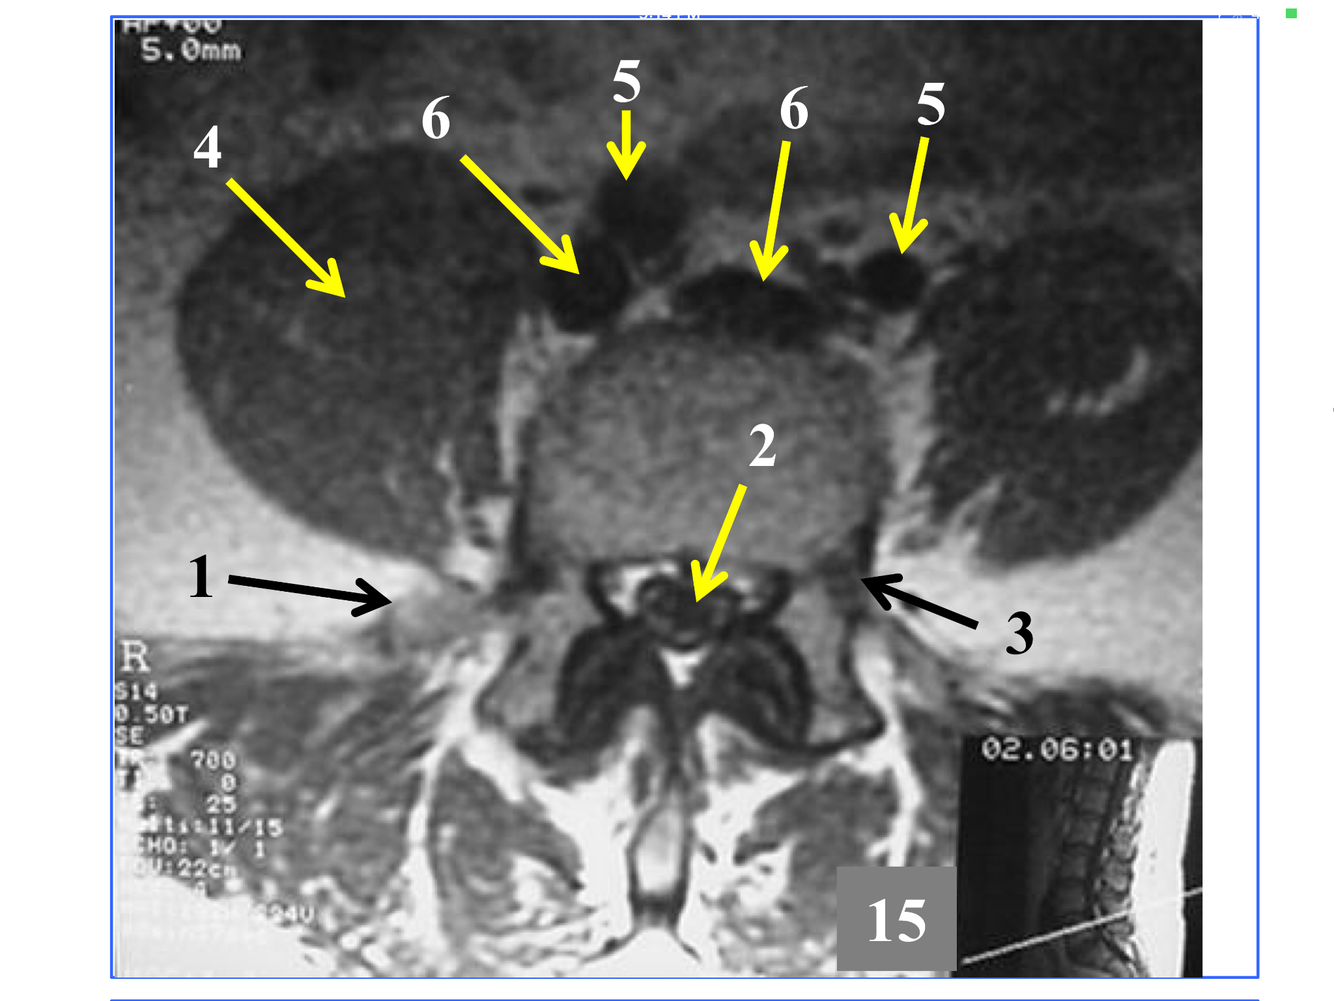

*Appears as streak as it heads fo rmidline in front of the medulla oblongata, to join the Rt vertebral and form the basilar A at the inferior and anterior to the pons.

** At the foramen magnum, entering the posterior fossa of the cranium.

**10. Rt & Lt vertebral arteries**